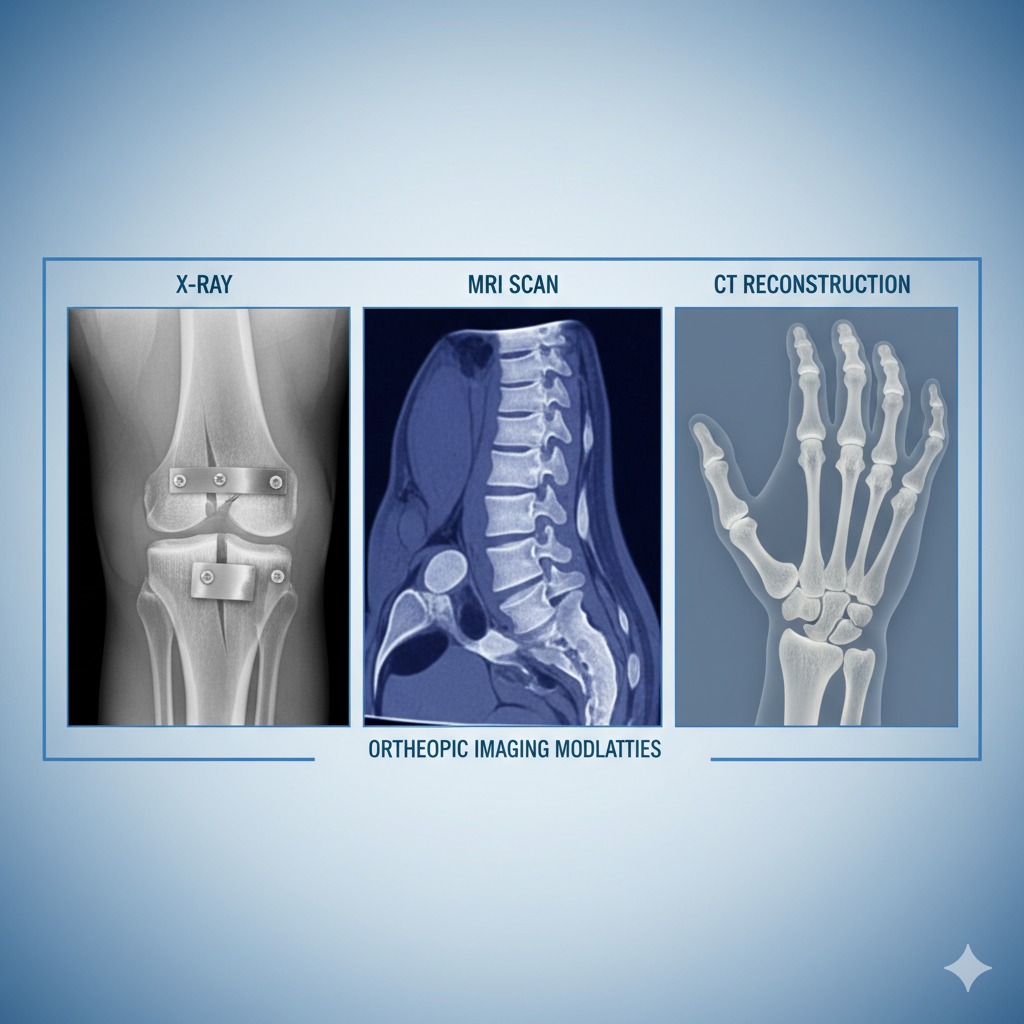

Radiology & Diagnostic Imaging Services in Delhi

Radiology is a vital medical specialty that uses advanced imaging techniques to diagnose and monitor a wide range of health conditions. From X-rays and ultrasounds to CT scans and MRI, radiology plays a crucial role in early detection, accurate diagnosis,

Best Orthopedics with Joint Replacement in kadkhoda Sonipat | Orthopedic Specialist

Orthopedics with Joint Replacement focuses on the diagnosis and treatment of bone, joint, and musculoskeletal disorders using advanced medical techniques. This blog explains knee, hip, and shoulder joint replacement procedures, their benefits, who needs j